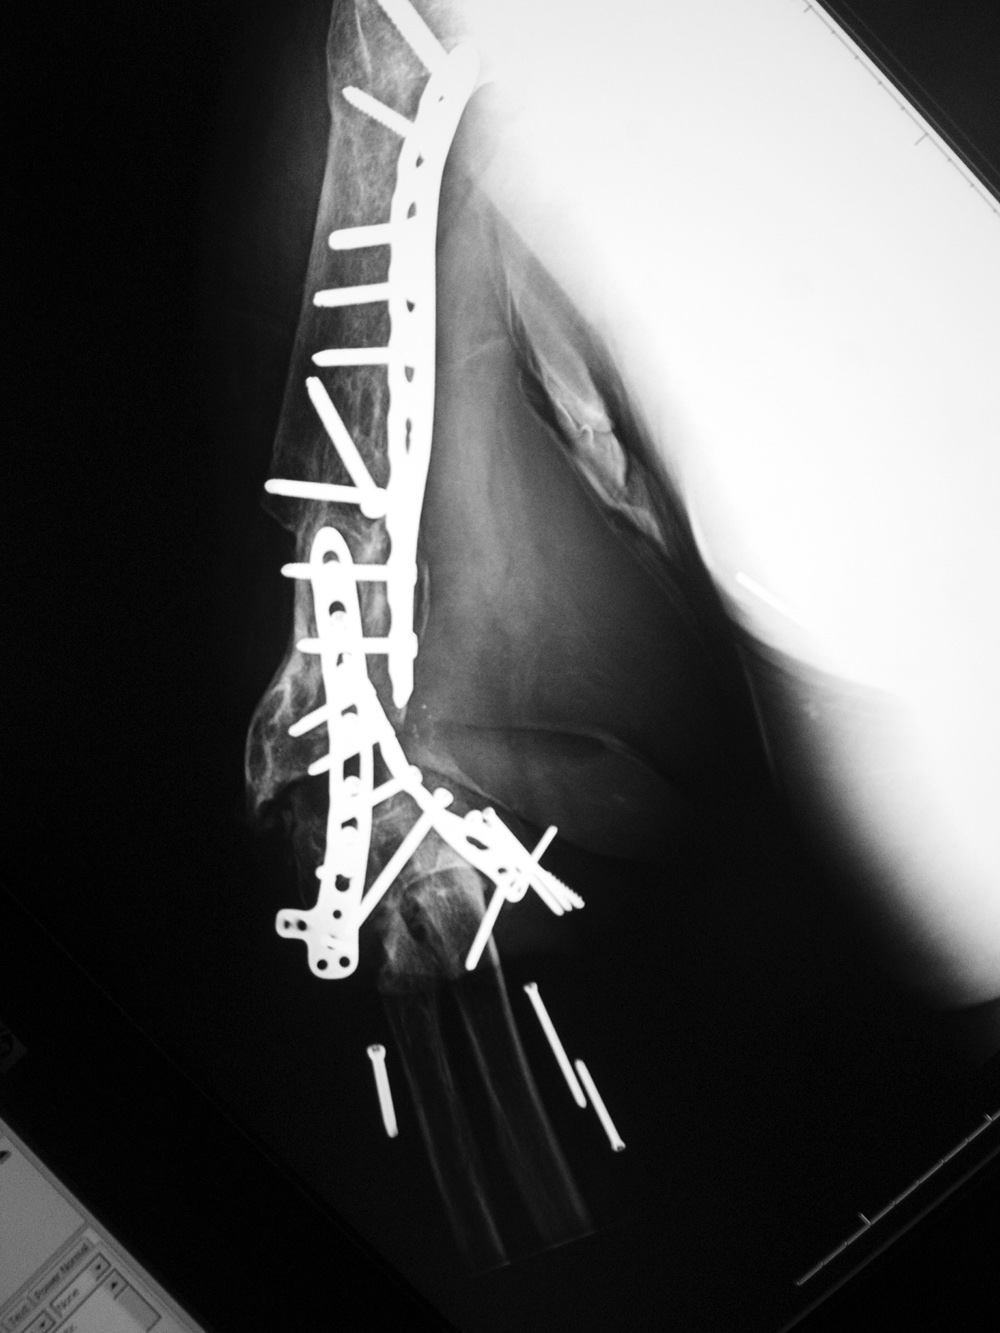

| Right femur periarticular plate breakage and chronic fracture nonunion |

| 36 year-old man with bullet wound in 2003 complicated by femur fracture infected non-union treated by multiple attempts with external fixation and open reduction and internal fixation (ORIF). Radiography 12 years later shows chronic fracture hypertrophic nonunion, multiple shrapnel fragments, and breakage of a periarticular fixation plate. |